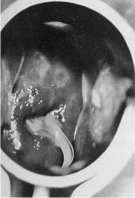

1.4.2.7.3三、临床表现